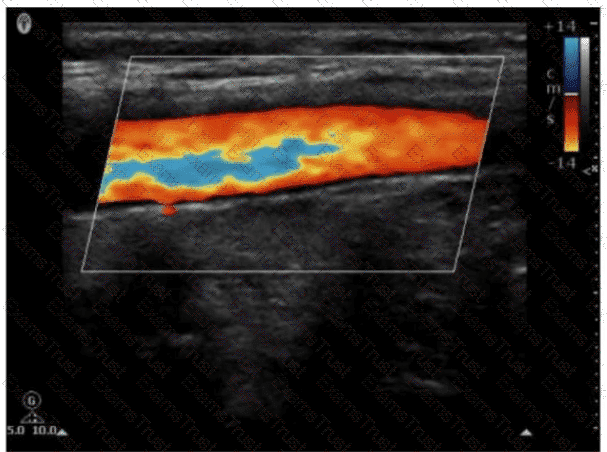

Question 28

Which pulsed-wave Doppler adjustment would be appropriate to correct the aliasing seen in this image?

Options:

A.

Increase the spectral Doppler gain.

B.

Decrease the spectral Doppler gain.

C.

Increase the Doppler pulse repetition frequency.

D.

Decrease the Doppler pulse repetition frequency.